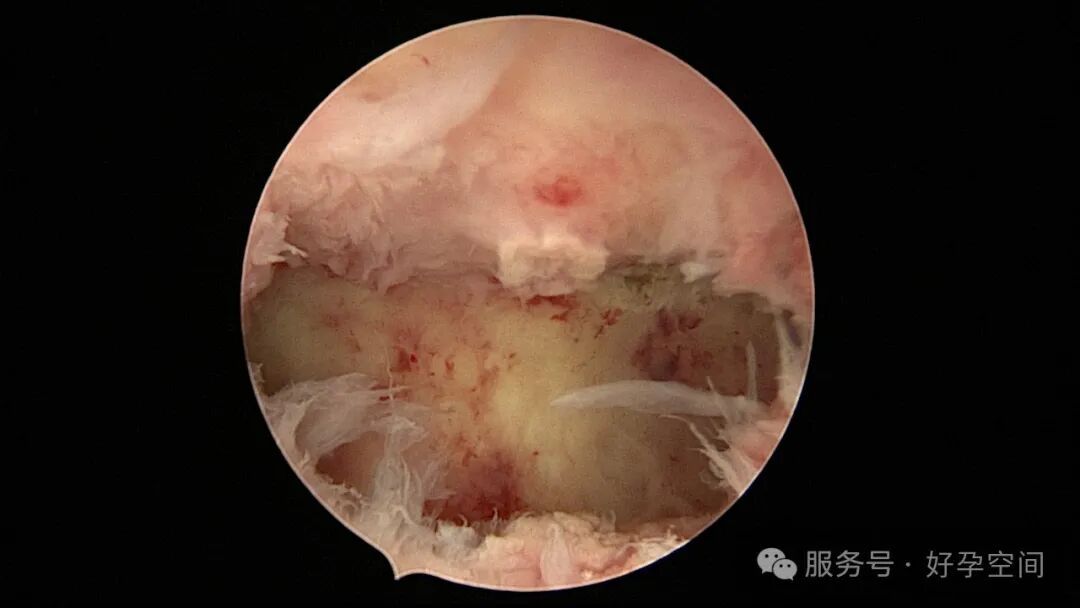

输卵管吻合术后妊娠,稽留流产,清宫术后宫腔粘连,宫腔镜单极电针分粘

分粘后宫腔镜二探,残留少许膜性粘连,镜鞘分粘